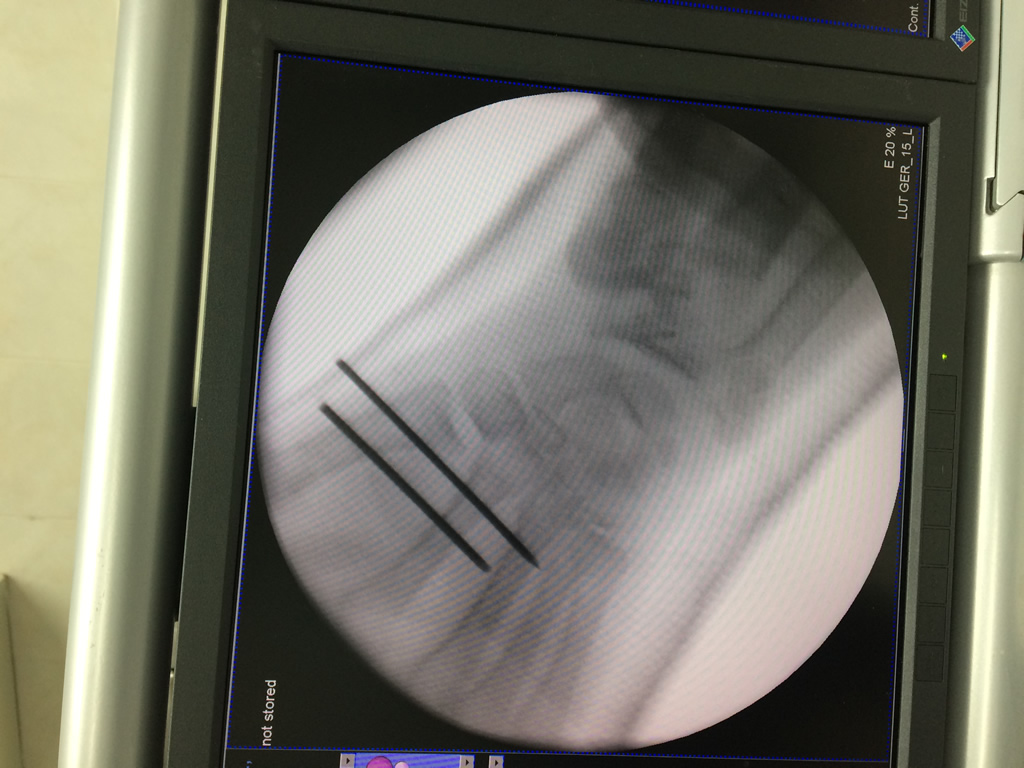

Cirugía de Fémur - Cirugías de Muñecas y Manos

Los procedimientos más comunes en cirugía de la mano son aquellos destinados a reparar traumatismos, incluyendo lesiones de tendones, nervios, vasos sanguíneos, y articulaciones; huesos fracturados; y quemaduras, cortes, y otros daños de la piel.